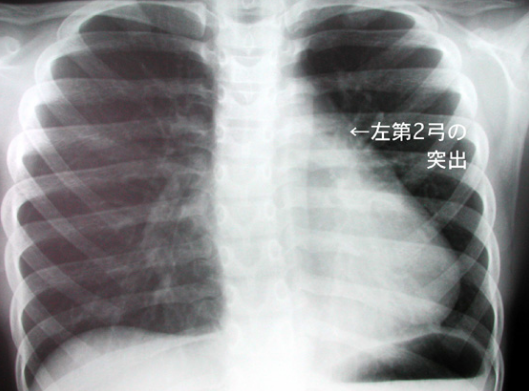

【左2弓の突出】

左2弓は肺動脈を反映している陰影である。左2弓突出の原因としては肺動脈に負荷のかかる疾患(ex.ASDやVSDなどの左右シャント、肺高血圧、肺動脈弁狭窄、貧血による血流増加など)

【左2弓の突出のもう一例】(ASD)